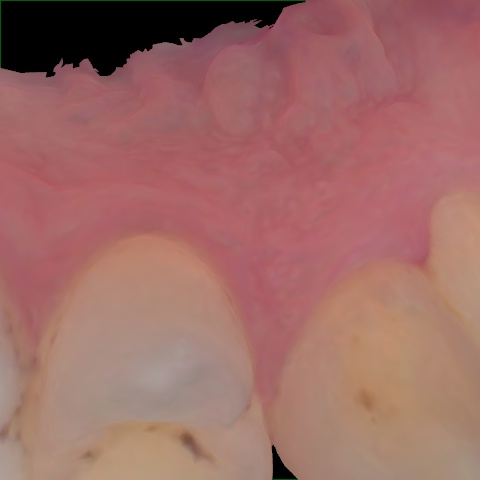

Annotated as "Good"

Original Image Rendering Image